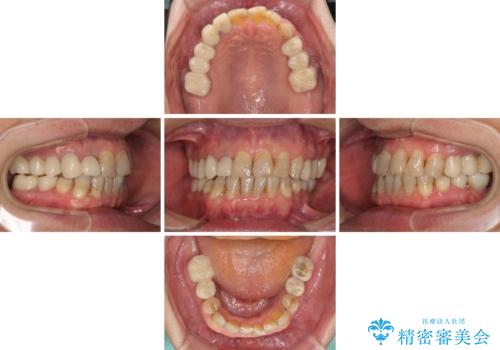

矯正治療を希望して来院されましたが、歯周病を併発していたため、矯正治療開始前の処置が非常に多くなりました。特に歯槽骨の再生治療を行ったため、外科処置後の静置期間が長くなり、4年弱の治療期間となりました。

治療後には咬みやすさだけでなく、前歯が大変審美的に仕上がり、患者様には大変満足していただきました。